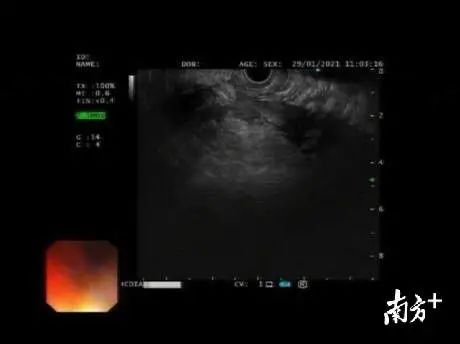

在南方医科大学南方医院对口帮扶专家、教授李跃带领下,消化疾病诊疗中心医疗团队成功完成中山地区乃至珠中江地区首例胰腺假性囊肿超声内镜下穿刺内引流术。术中置入导丝后用囊肿切开刀切开胃壁和囊肿壁,通过导丝成功植入10-F双猪塑料支架,将假性囊肿与胃腔连通,使囊液通过胃腔自然排除,全程包括准备时间短短30分钟, 术后超声内镜下可见囊肿消失。